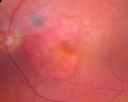

85-year-old woman has age-related macular degeneration in both eyes with geographic atrophy. She has noticed her vision getting slightly worse since I saw her last in December.

VISUAL ACUITY: OD 20/70, OS 20/400. IOP: OD 12, OS 17. She has low filtering blebs in both eyes. There is a posterior chamber intraocular lens is in good position in both eyes.

OD: Vertical C/D ratio is 0.5. There is geographic atrophy. There is no intraretinal or subretinal fluid.

OS: Vertical C/D ratio is 0.5. There is geographic atrophy. There is no intraretinal or subretinal fluid.

FLUORESCEIN ANGIOGRAPHY: Fluorescein angiography shows concentric geographic atrophy, predominately nasal to the fovea in each eye. The geographic atrophy is unfortunately now closer to the foveal center.

DISCUSSION: I explained to the patient that the macular degeneration does look slightly worse and although she only notices a slight decline in vision, her vision in fact measures substantially worse than it did when she was last here. When I saw her in December she was seeing 20/40 out of both eyes and now she is down to 20/70 and 20/400. Sometimes patients with geographic atrophy can develop seemingly sudden vision loss when the geographic atrophy progressed to involve the center of the macula.